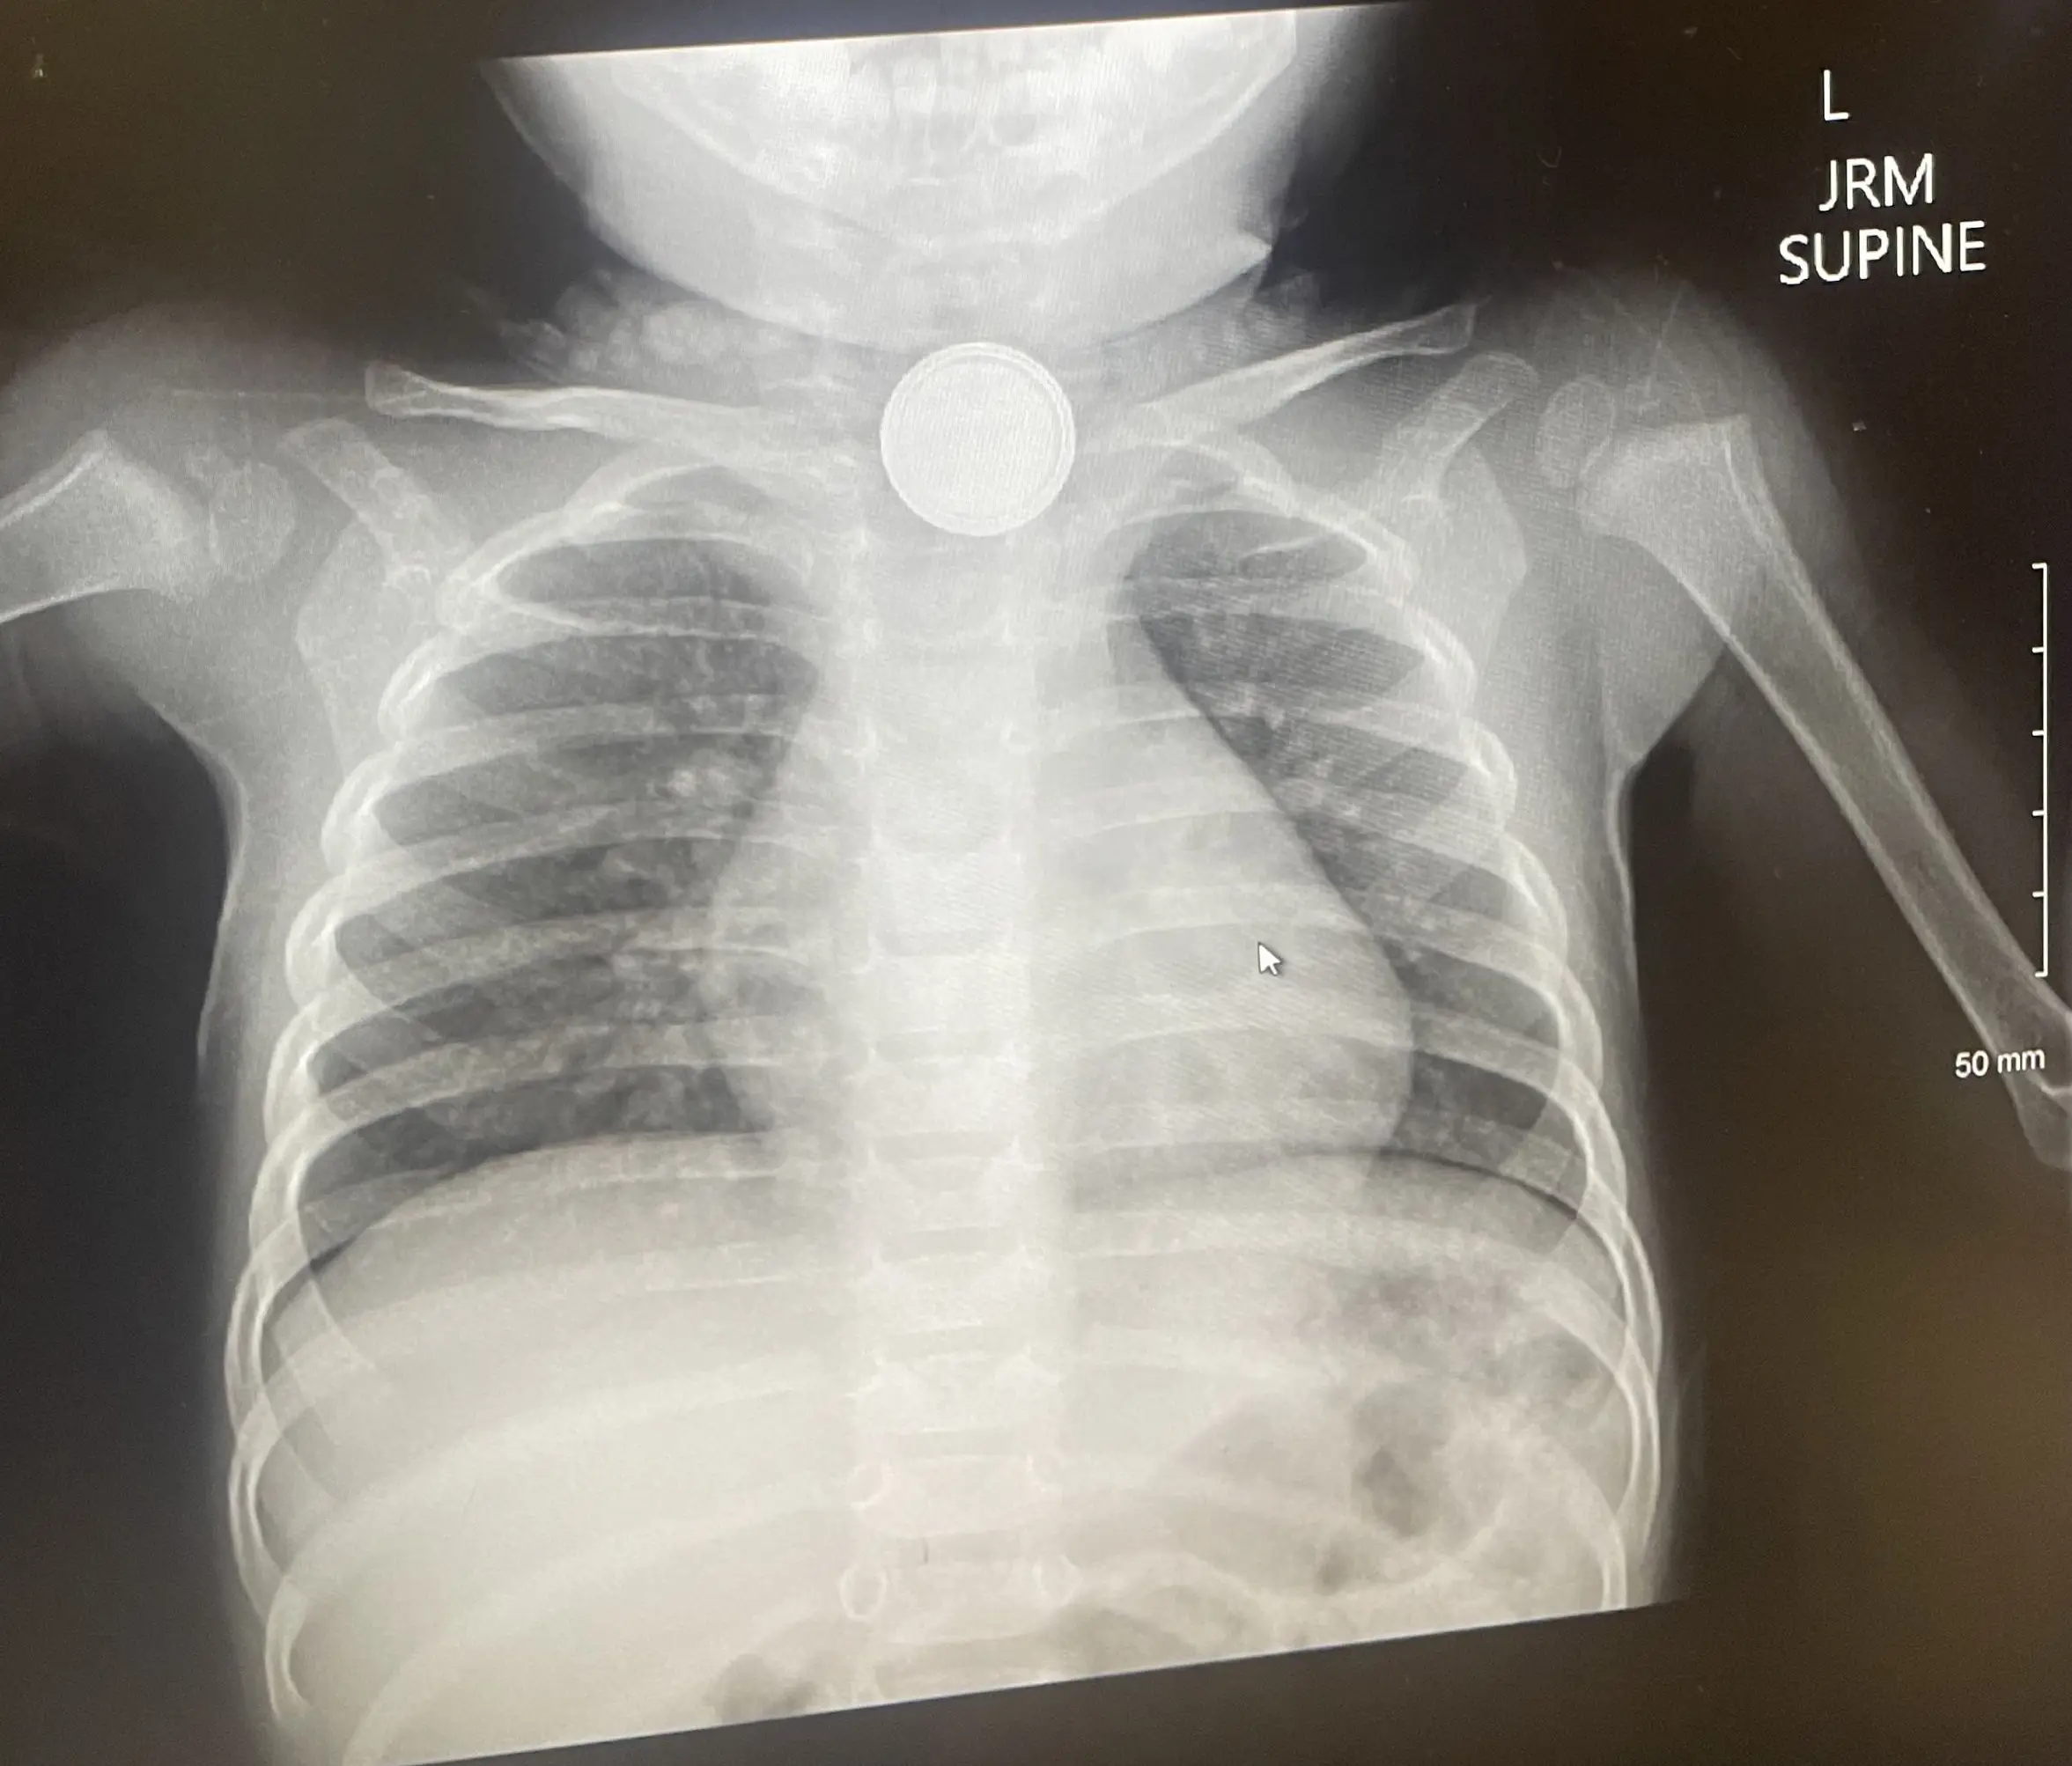

A harrowing X-ray of the young boy's oesophagus revealed that the battery was lodged right in there.

"They did the X-ray and he had swallowed the battery which was lodged between his collarbone. From there, they transported us to a bigger hospital and they needed three doctors to get it out," she recalled.